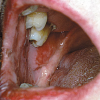

Suu limaskesta haavandid

- Alati tuleb kontrollida hambaproteese. – Haavandi põhjuseks võib olla odontoloogiline infektsioon. – Igal juhul tuleb arvestada vähi võimalusega. Reeglina tuleb võtta biopsia haavanditest, mis kahe nädala jooksul ei parane....